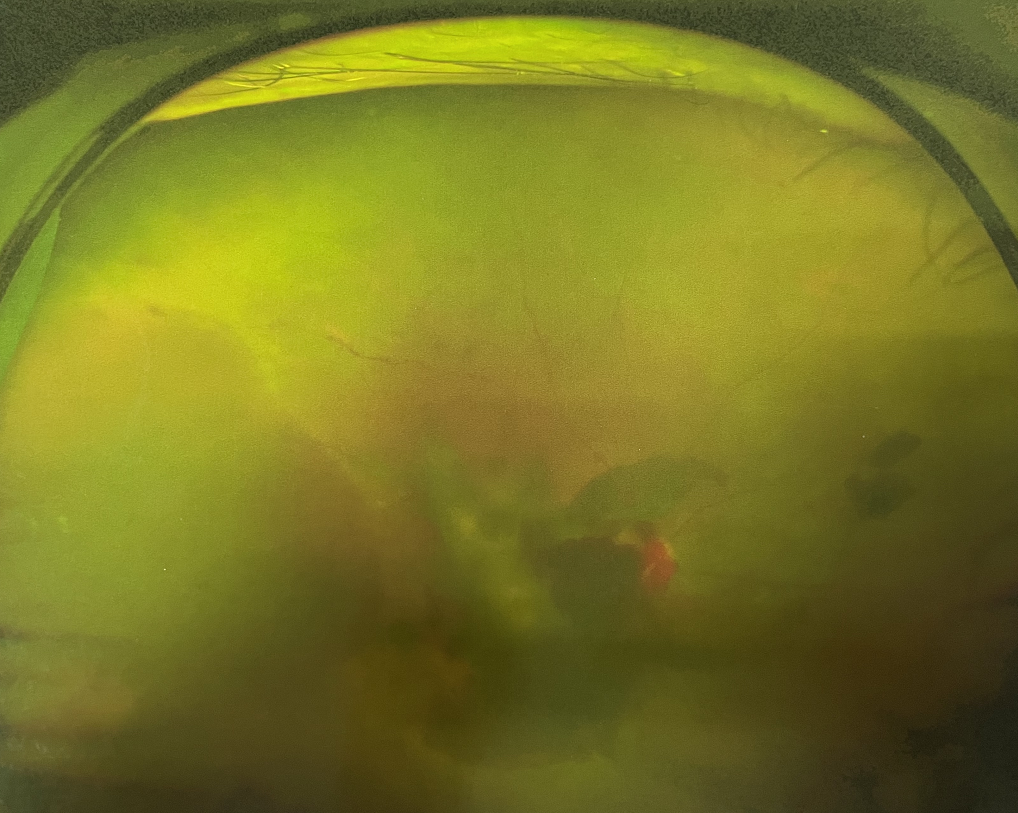

四十多歲的王女士,患高血壓病及Ⅱ型糖尿病多年,一直靠藥物控制血壓和血糖。去年,王女士右眼看手機時感覺視物不清,總感覺眼前有一層霧,視力也逐漸下降,于是來廈門大學(xué)附屬廈門眼科中心就診。

眼底病??茝埿』⑨t(yī)生檢查后,診斷王女士為“雙眼玻璃體積血、雙眼糖尿病視網(wǎng)膜病變V期”。(V期即5期,纖維增生期,出現(xiàn)纖維膜,可伴視網(wǎng)膜前出血或玻璃體出血。)

張小虎醫(yī)生為王女士進行右眼玻璃體腔注藥術(shù),3天后進行右眼23G玻璃體切割術(shù)后視力有所提升。

4個月后王女士來院取硅油,取油后視力恢復(fù)到0.6。“當時來的時候真的只能看到模糊的影子,特別害怕覺得完了,想說眼睛估計要瞎了,沒想到手術(shù)后視力竟然提升了,現(xiàn)在也看得比較清楚了。”王女士說到。

張小虎醫(yī)生表示,糖網(wǎng)病進展到嚴重增殖期帶來的視力損傷往往是極其嚴重的,目前王女士右眼從術(shù)前0.02恢復(fù)到術(shù)后0.6,已屬十分難得。

右眼術(shù)前